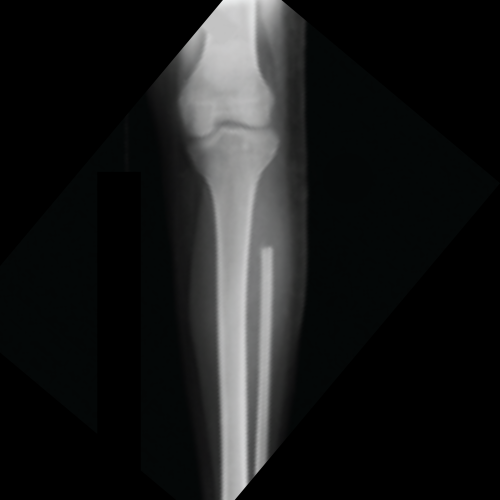

after image of tumours

After Tumour Surgery